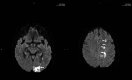

A 71-year-old lady presented with a symptomatic left cerebral occipital lobe infarct. With a history of paroxysmal atrial fibrillation a cardioembolic source was initially postulated. Prior significant bleeding while anticoagulated precluded warfarin therapy. Further investigations revealed a critical left internal carotid stenosis with a persistent fetal origin of the left posterior cerebral artery. She was successfully treated surgically and suffered no further ischaemic events. Physicians encountering posterior circulation stroke should be aware of this potentially treatable important diagnosis.